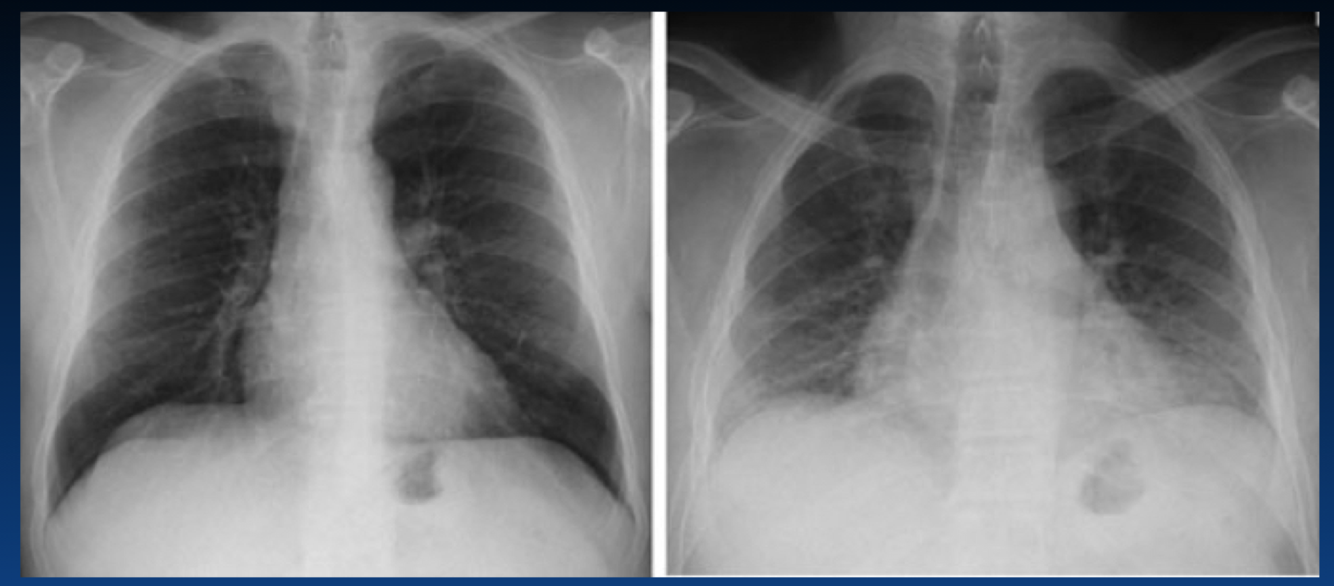

This does not show a real increase CTR. Why?

You can tell an expiration by the height of diaphragm as well as counting the ribs (the right only shows 4 ribs). You should see 6 or 7 ribs.